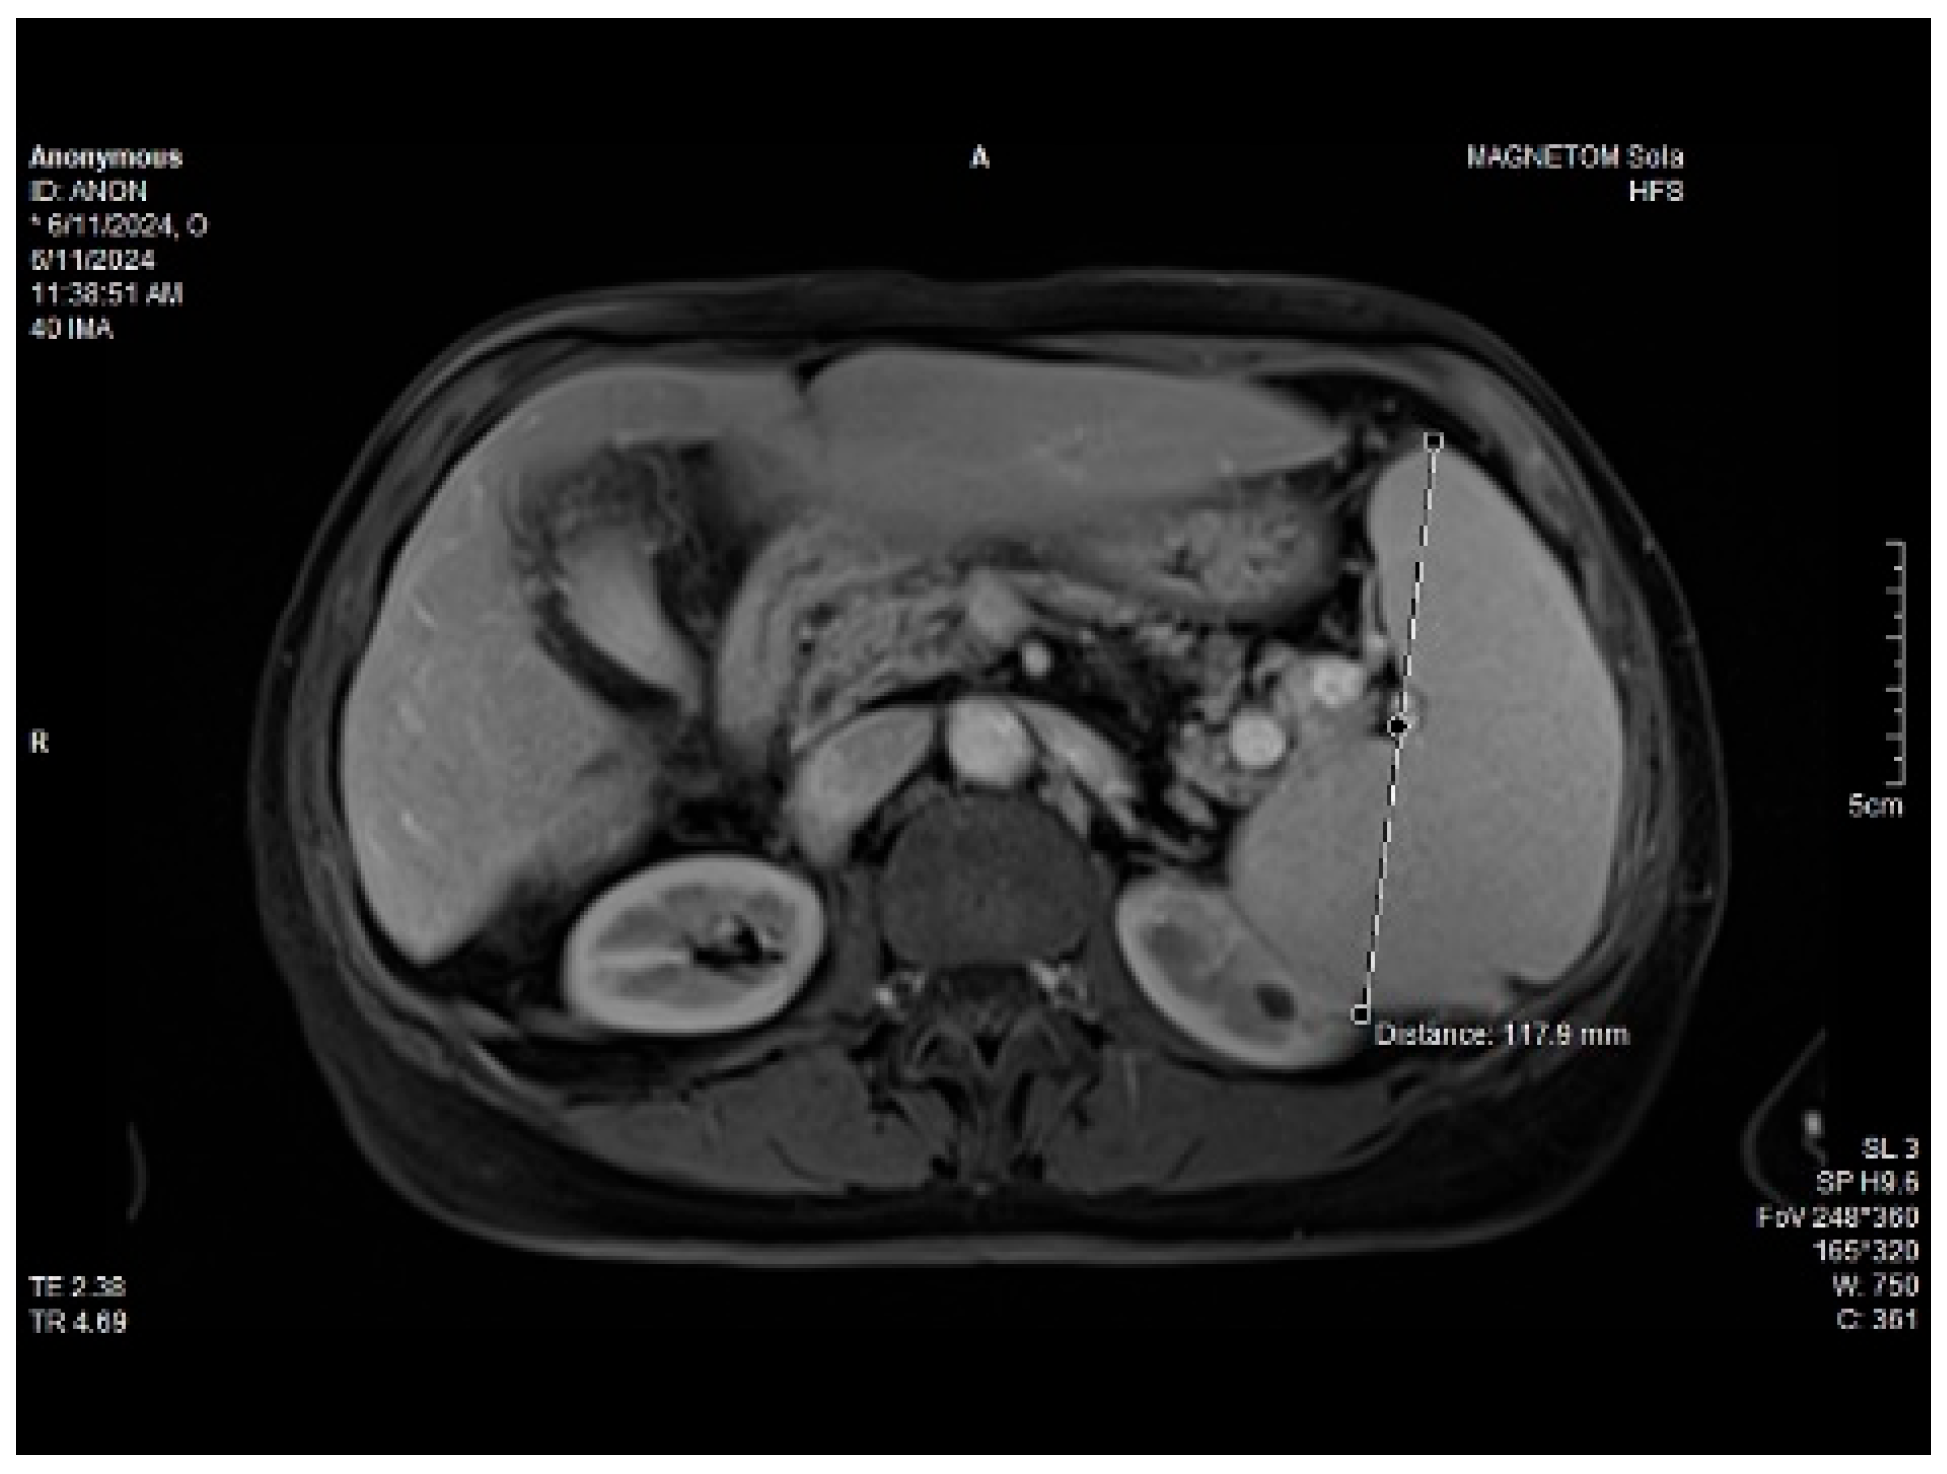

The measurements of the resistivity index of the hepatic artery at the liver hilum revealed increased values (HARI = 0.79). However, the liver elastography demonstrated a low stiffness. The measurements were made using the acoustic radiation force impulse (ARF)I method, by point shear wave (p SWE) elastography, and the obtained median value was 1.24 m/s, IQR = 0.12, equivalent to an F2 Metavir fibrosis score. Therefore, the diagnosis of liver cirrhosis was highly improbable. The elastography of the right liver lobe performed by the ARFI method, pSWE, is presented in Figure 5.

Figure 5. p SWE elastography of the right liver lobe.